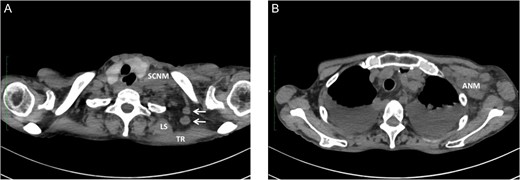

A 76-year-old male underwent screening endoscopy because of a history of gastrectomy for cancer, which showed a superficial and protruding tumor in the mid-thoracic esophagus. Histological examination of the biopsy specimen confirmed well-differentiated squamous cell carcinoma. A computed tomography (CT) scan of the neck, chest and abdomen showed no evidence of metastatic disease. The tumor was clinically staged as T1bN0M0 according to the American Joint Committee on Cancer [1]. He received concurrent chemoradiotherapy at a dose of 60 Gy with low-dose 5-fluorouracil. Four months after completion of chemoradiotherapy, however, the primary tumor relapsed with mediastinal LNM and right SCNM. Right transthoracic esophagectomy with mediastinal and right cervical lymphadenectomy was performed as a salvage treatment. Two months after esophagectomy, a right neck tumor developed that was palpable at the posterior triangle, close to the anterior border of the trapezius muscle. A CT scan of the neck showed a heterogeneously enhanced tumor 25 mm in diameter located between the trapezius muscle and the levator scapulae muscle (Fig. 1). En bloc dissection of the adipose tissue including the tumor and the transverse cervical artery was performed. Histological examination revealed that 5 of the 22 retrieved lymph nodes had metastatic squamous cell carcinoma. The patient received adjuvant radiotherapy of 50.4 Gy to the area of dissection; however, died of pneumonia 11 months after metastasectomy, with locally recurrent disease that invaded right brachial plexus.

Note that the transverse cervical vessels (*) were involved in the tumor (arrow). TR, trapezius muscle; LS, levator scapulae muscle.